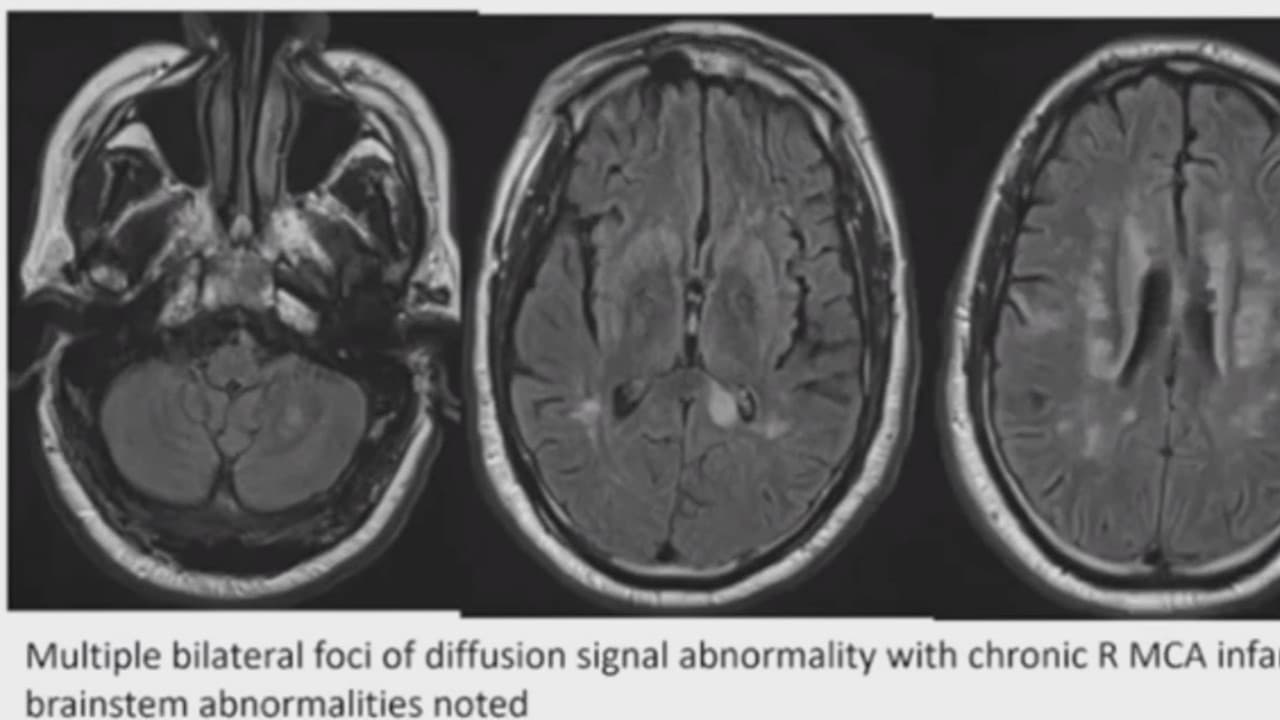

El doctor Gabriel de Erausquin, investigador y neurólogo, es el autor de un estudio que muestra que los efectos en el cerebro de personas contagiadas con coronavirus pueden tener largos alcances.